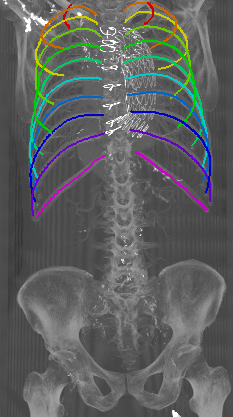

Refer to caption

Figure 5: Automatically generated centerline splines associated with the FCNN outputs displayed in Figure 4. The selected case above display common difficulties which are inherent in the data set, such as pads (a) or cables (b), internal devices such as pacemakers (c), stents (d), spinal (e) and femural/humeral implants (f), injected contrast agents (g), patient shape variations such as scoliosis (h), limited field of views (FOVs), i.e. partly missing first (i) or twelfth rib (j).

With an average Euclidean distance error of 0.787 mm, we obtained an overall result that is generally better compared to what is reported in the state of the art. Although, it needs to be kept in mind that results are unfortunately not directly comparable as both the data sets as well the evaluation metrics significantly differ across prior work. Similarly to the results obtained on the probability maps, distance errors are significantly higher for first and twelfth rib compared to the rest of the rib cage. As discussed, this is caused by the intrinsic challenges of these ribs, but certainly also an affect of error propagation in that sense that the quality of the probability maps also impacts centerline extraction. Interestingly, the right ribs are generally slightly worse compared to the left ribs, probably due to a slightly unbalanced data set with more challenges on the right side. Figure 5 shows the centerlines which were automatically generated using our walker algorithm from the corresponding network outputs displayed in Figure 4.